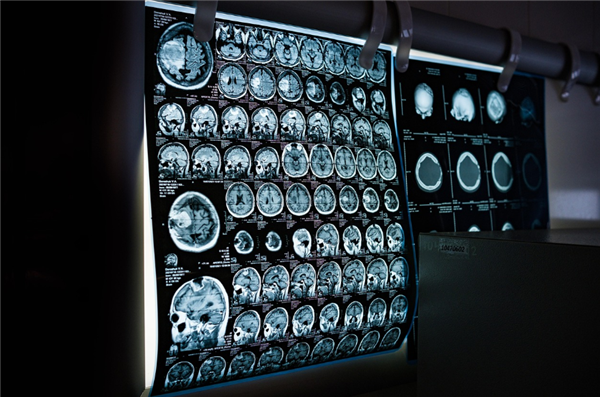

市民黄女士的接诊医师也深有感触,通过广东影像云平台调阅影像来诊断,精准度也比传统胶片更高。患者带来的胶片有时看不清楚,在电脑上打开的电子影像可以清晰看到更多细节,还方便放大缩小等操作。